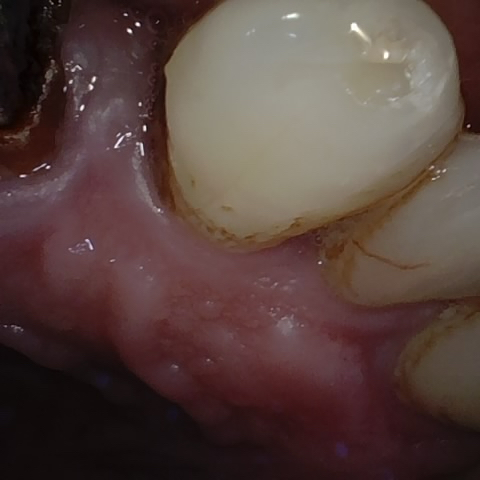

Annotated as "Good"